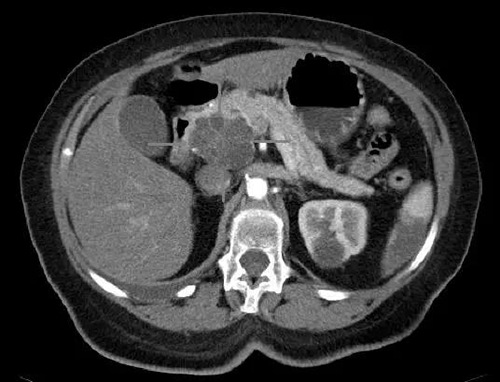

иғ°еӨҙзҷҢе’ҢеӣҠи…әзҷҢе…·жңүivжҜ”з…§еәҰзҡ„иҪҙеҗ‘CTеӣҫеғҸпјҲеӣҫзүҮжіүжәҗ:Scienceпјү